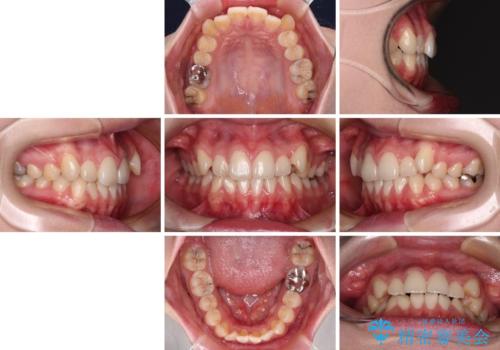

八重歯を確実に改善 補助装置を併用したインビザライン矯正治療

- 左右の八重歯を気にして来院された患者様です。

歯列としてはインビザラインでもワイヤー矯正でも対応できるものでしたが、インビザラインによる治療を希望されていました。

上顎の八重歯改善にインビザラインでは時間のかかってしまう可能性があり、更には口元が治療前よりも突出してしまう可能性があったため、補助装置により八重歯を事前に引き込んでおくことで、インビザラインによる治療をスムーズに行えるように計画しました。

補助装置を使用したことで、口元が突出することもなく、スムーズに仕上げることができました。